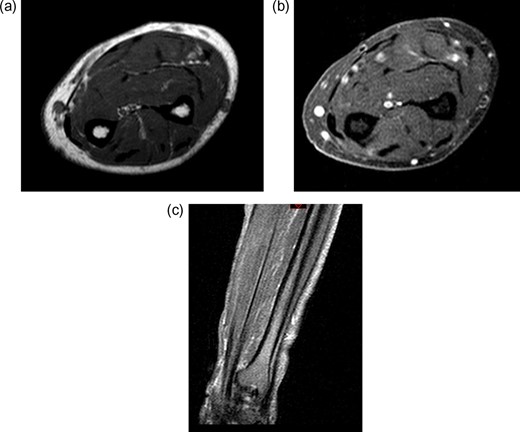

A 71-year-old male was referred to sarcoma clinic on 11/9/2017 with a painless swelling in his right forearm. He had a previous history of primary retro-peritoneal leiomyosarcoma surgery in 2011 with subsequent liver and lung metastases for which he underwent surgical resection in January 2017. His other past medical history included benign prostatic hypertrophy (controlled with medication), otherwise he was fully mobile, fit and well. This right-hand dominant male described a gradual 3-month history of increasing painless swelling to the volar aspect of the right forearm with full function of the arm and no neurological deficit. On clinical examination, there was a soft 5 × 4 cm swelling, 5 cm proximal to wrist crease in the volar compartment of the right forearm. The swelling was fixed, non-tender with no distal neurovascular deficit and or regional lymphadenopathy. Magnetic resonance imaging (MRI) of the right forearm demonstrated a 45 × 33 × 19 mm mass in the volar aspect in close relation to the median nerve (Fig. 1). Ultrasound-guided needle core biopsy was consistent with LMS and the histology was similar to the previous LMS suggesting the possibility of metastatic LMS. Staging studies did not show any other metastatic deposits. Following multidisciplinary team discussion, he underwent planned marginal excision of the metastatic sarcoma with preservation of the median nerve. Histology confirmed LMS composed of spindle cells with eosinophilic cytoplasm with mild pleomorphism confined within the perimysium with no necrosis or vascular invasion (trojani grade 1). The patient recovered well post operatively with no neurological deficit only complicated with a mild episode of cellulitis to the wound site which fully resolved with a short course of oral antibiotics. One year after surgery, the patient has full function and use of his right hand and there is no evidence of LMS recurrence or further metastatic spread both clinically and radiologically on recent CT scan of his chest, abdomen and pelvis and MRI scan of the forearm (Fig. 2).

Post-treatment contrast MRI of the forearm showing curative resection and no evidence of recurrence in the flexor compartment (a) sagittal T1, (b) sagittal T2 and (c) coronal T1.